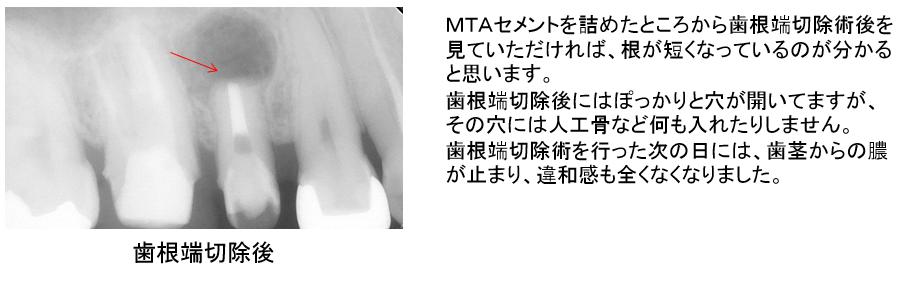

まずは以前に詰めてある根管充填剤を全て除去し徹底的に根管内をきれいにしMTAセメントで埋めなおします。

歯根端切除術後です。

根の先端が短くなっているのが分かると思います。